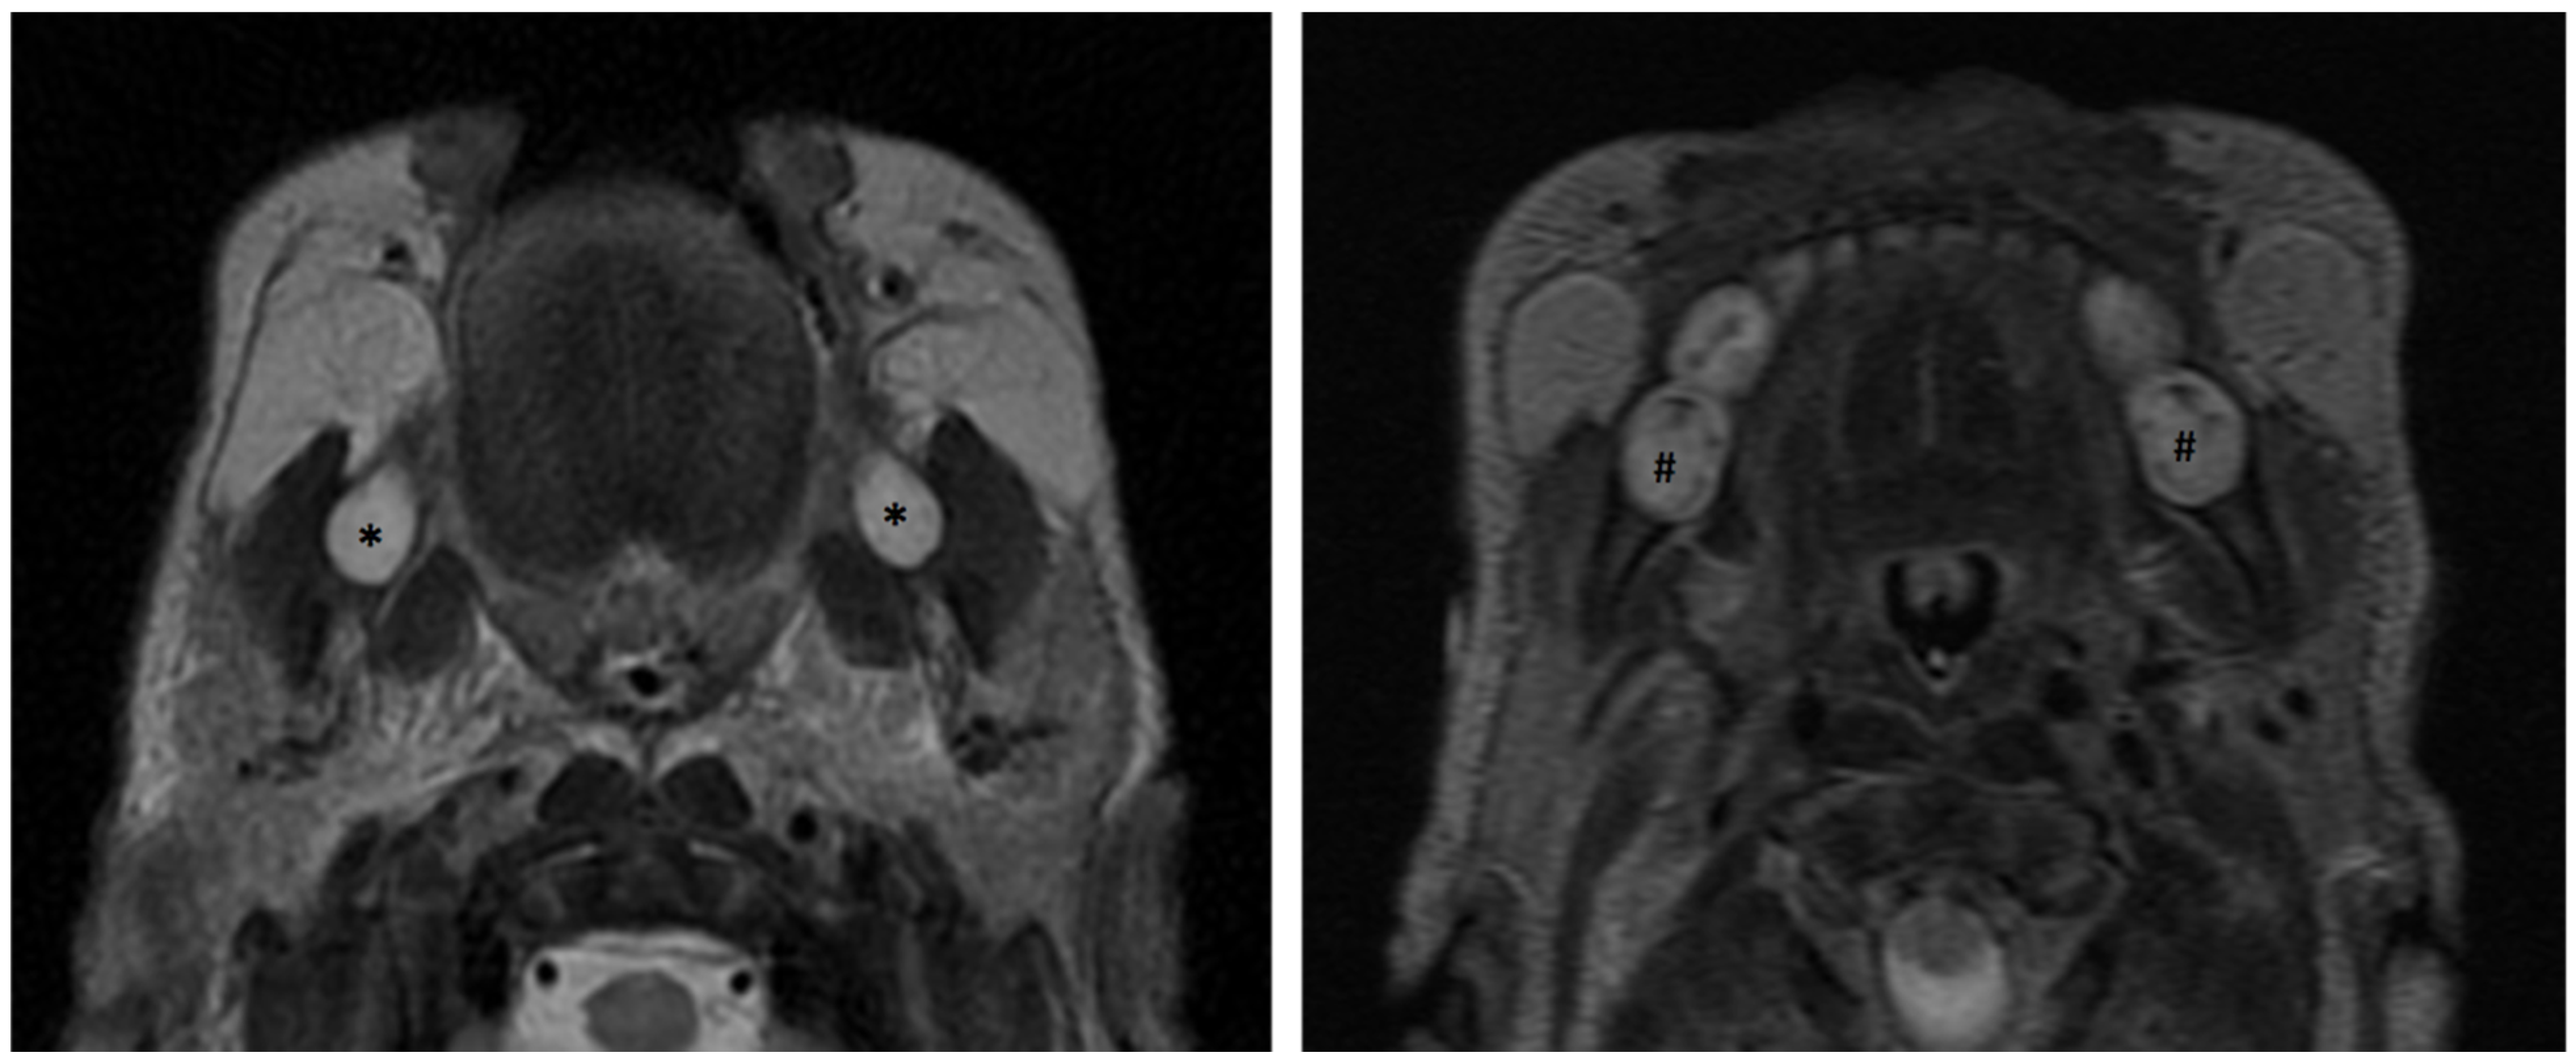

3.4. Application of Principles to Consecutive MR Exams

3.5.2. Dental Decay Radiologic Correlations

3.5.4. Periodontal Disease Radiologic Correlations